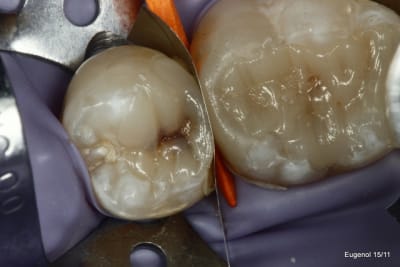

un truc que je fais souvent, quand je monte deux compo volumineux en contact, je monte le plus gros et difficile sans matrice et comme ça j'ai accès a la marge, et je peux donner une jolie forme galbée proximale

puis je monte le suivant avec une seule matrice...

plus facile je trouve d'avoir le point de contact